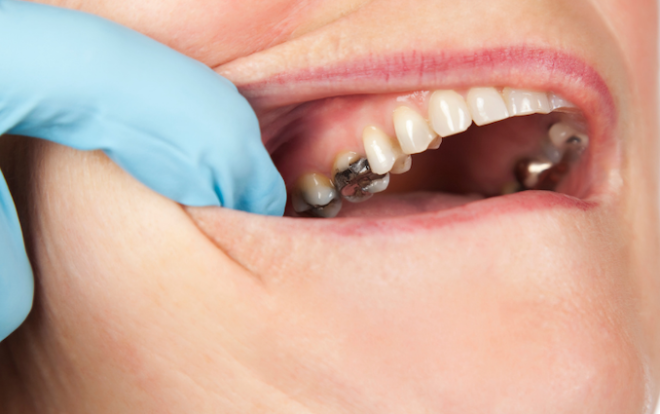

Cáries extensas

Lesões cariosas profundas podem afetar a polpa dentária, causando dor intensa. O tratamento imediato, por meio de restaurações diretas ou indiretas, evita complicações como infecções e necessidade de intervenções mais invasivas.